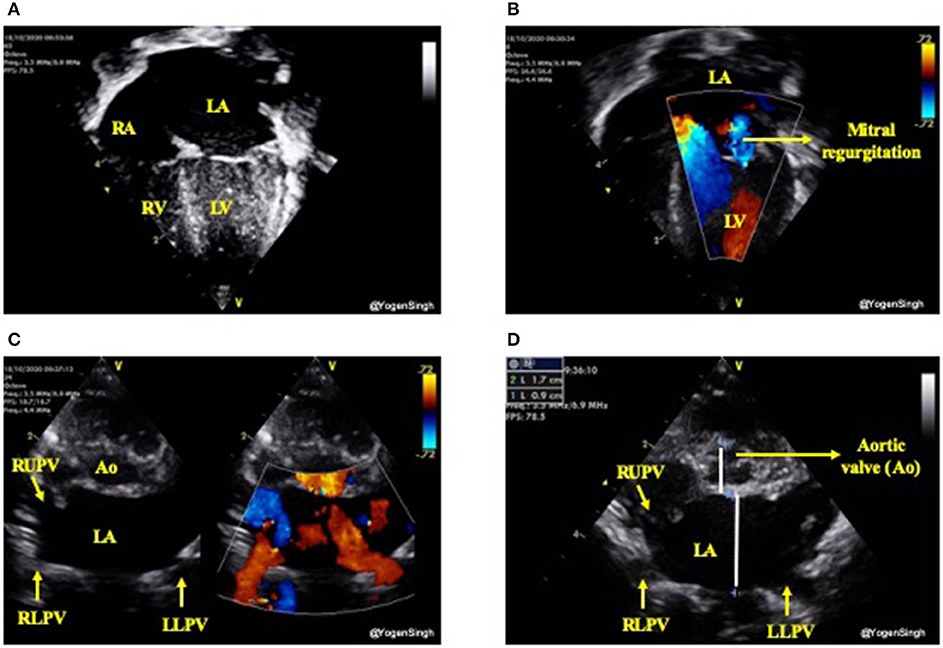

The increased pulmonary blood flow from a significant left-to-right ductal shunt leads to pulmonary blood flow and hence increased pulmonary venous return. This leads to increased volume overload in the left atrium (LA) which gradually gets dilated and if this process of significant left to right shunt persists then it leads to dilatation of left ventricle from increased preload, especially in absence of a large intra-atrial shunt. As aortic valve annulus (Ao) is a relatively fixed structure and it does not get dilated due to left heart overloading. Hence, a ratio of LA/Ao can be used as a surrogate of increased pulmonary venous return (24, 25). Similarly, the left ventricular end diastolic diameter (LVEDD) can be used as surrogate markers for pulmonary venous return. In clinical practice the volume overloading of the left heart can be subjectively assessed by “eyeballing” (15) (Figure 6).

Figure 6. Assessment of left heart volume overloading on visual inspection “eyeballing.” (A) Apical 4 chamber view in 2D showing dilated left side of the heart (dilated left atrium and left ventricle); (B) Mitral regurgitation on color flow mapping as blue jet going back to left atrium (see explanation in text); (C) “Crab view” showing dilated pulmonary veins reflecting increased pulmonary venous return and (D) Dilated left atrium in parasternal short axis view—on visual inspection LA looks almost the double the size of aortic valve (Ao). LA, left atrium; LV, left ventricle; RA, right atrium; RV, right ventricle; Ao, aortic valve; RUPV, right upper pulmonary vein; RLPV, right lower pulmonary vein; LLPV, left lower upper pulmonary vein.

Both LA/Ao ratio and LVEDD can be measured from the parasternal long axis view using M-mode with the cursor perpendicular to the aorta at the level of the aortic valve or at the septum at the tip of the mitral valve leaflets, respectively (Figure 7). LA/Ao ratio of >1.4 is considered significant and has been used as a cut-off value in many clinical trials (25). The normal reference ranges for LVEDD in preterm infants in relation to body weight and postnatal age have been published and z-scores should be used for LVEDD (26).

Variable degree of mitral valve insufficiency is often seen in infants with persistent large PDA and significant left heart dilatation (Figure 6). It occurs due to left atrial dilatation resulting in stretching of mitral valve and left ventricular volume-overloading. The mitral valve regurgitation usually improves significantly with normalization of left atrial size and resolves completely within weeks after PDA closure (14, 26, 27).